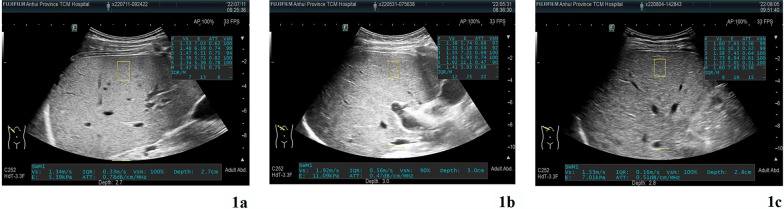

The level of ATT was significantly different within three groups (P < 0.001). Compared to each other, the levels of FIB-4, APRI, and SWM were not significant different within three groups (P > 0.05) (Table 2). ATT measure images for each group were shown in Fig. 1 and ATT box plots were drawn for each group (Fig. 2). Significant differences were found in intergroup comparisons of ATT levels (Table 3).

Fig. 1.

ATT ultrasound images for 3 groups of patients with WD (a Group1, median of ATT is 0.75; b Group1, median of ATT is 0.68, c Group1, median of ATT is 0.56)